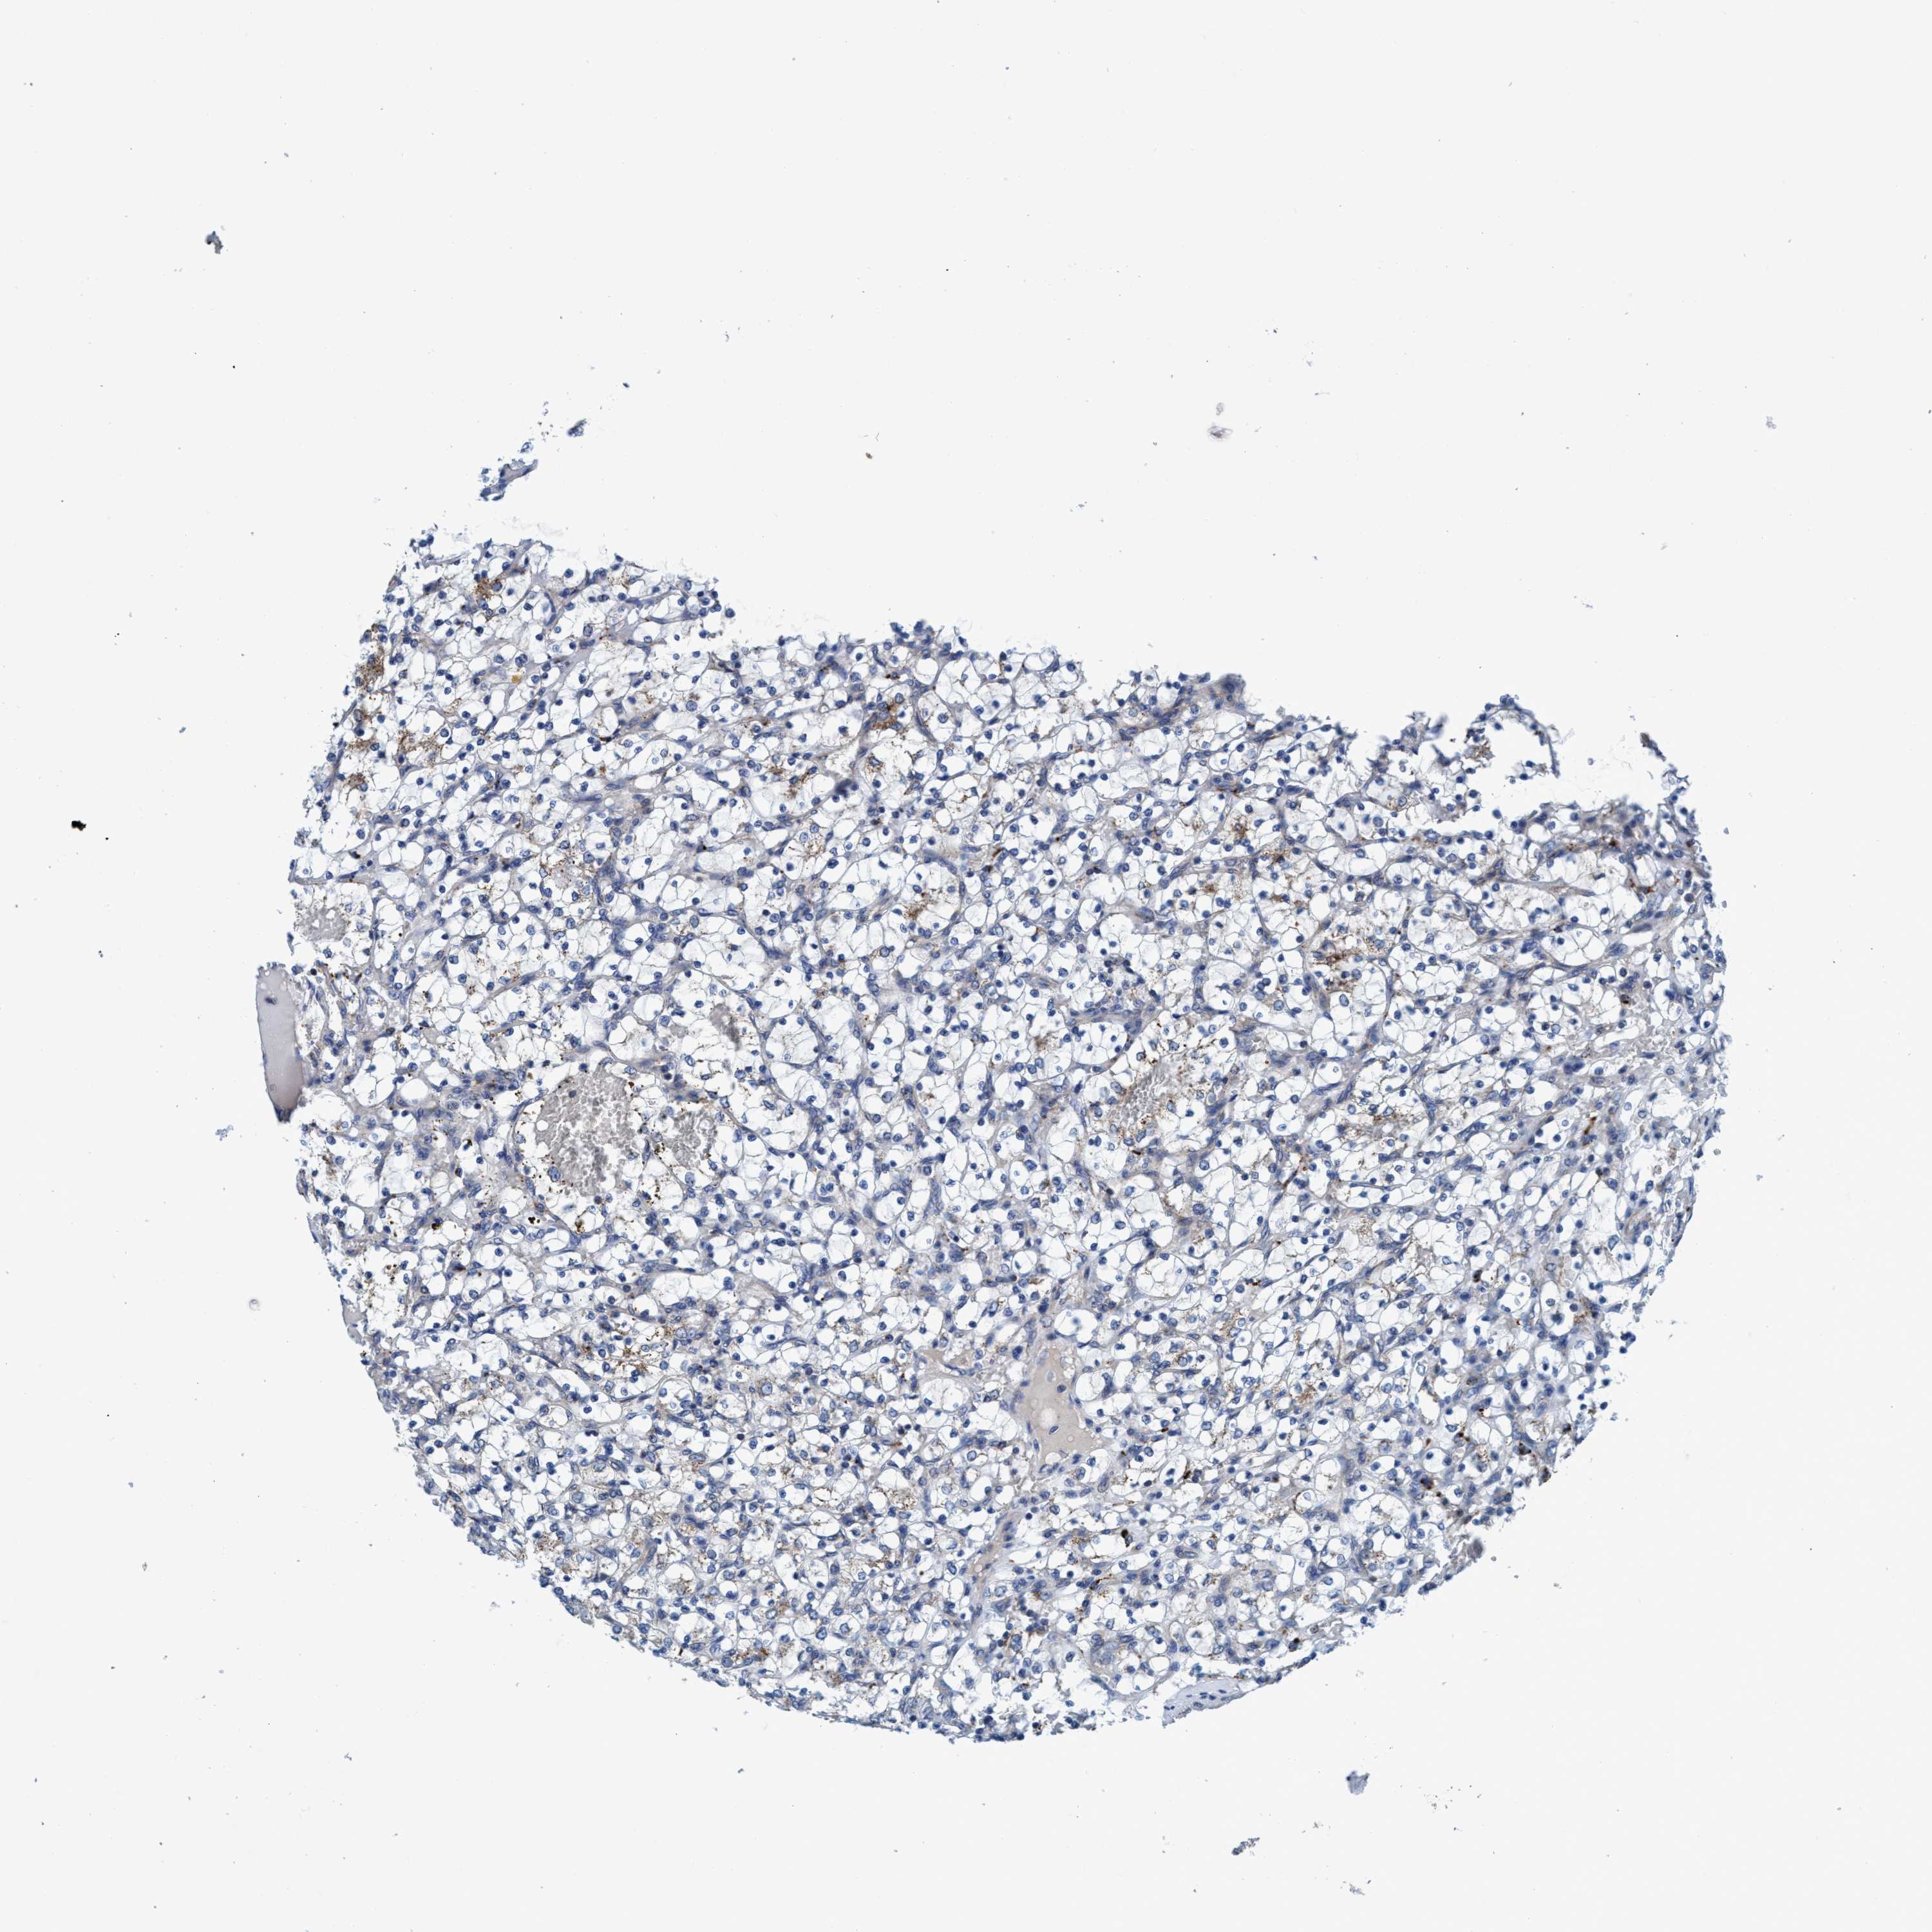

KIDNEY RENAL PAPILLARY CELL CARCINOMA (TCGA) - Interactive survival scatter ploti

The Survival Scatter plot shows the clinical status (i.e. dead or alive) for all individuals in the patient cohort, based on the same data that underlies the corresponding Kaplan-Meier plots. Patients that are alive at last time for follow-up are shown in blue and patients who have died during the study are shown in red.

The x-axis shows the expression levels (FPKM) of the investigated gene in the tumor tissue at the time of diagnosis. The y-axis shows the follow-up time after diagnosis (years). Both axes are complimented with kernel density curves demonstrating the data density over the axes. The top density plot shows the expression levels (FPKM) distribution among dead (red) and alive patients (blue). The right density plot shows the data density of the survived years of dead patients with high and low expression levels respectively, stratified using the cutoff indicated by the vertical dashed line through the Survival Scatter plot. This cutoff is automatically defined based on the FPKM cutoff that minimizes the p-score. The cutoff can be changed by dragging the vertical line or by entering a cutoff value in the square labeled "Current cut-off".

Under the Survival Scatter plot the p-score landscape (black curve; left axis) is shown together with dead median separation (red curve; right axis). Dead median separation is the difference in median mRNA expression between patients who have died with high and low expression, respectively. It is calculated as follows: median FPKM expression of dead patients with high expression - median FPKM expression of dead patients with low expression. This is intended to aid the user in visually exploring custom cutoffs and the associated p-scores and dead median separation.

Individual patient data is displayed and can be filtered by clicking on one or more of the category buttons on the top of the page. Categories describing expression level and patient information include: high, low, alive, dead, female, male and tumor stages. The scale of the x-axis can be toggled between linear and log-scale by clicking on the "x log" button. Mouse-over function shows TCGA ID, patient information and mRNA expression (FPKM) for each patient.

& Survival analysisi

Kaplan-Meier plots summarize results from analysis of correlation between mRNA expression level and patient survival. Patients were divided based on level of expression into one of the two groups "low" (under cut off) or "high" (over cut off). X-axis shows time for survival (years) and y-axis shows the probability of survival, where 1.0 corresponds to 100 percent.

ENDOG is potential prognostic, high expression is favorable in Kidney Renal Papillary Cell Carcinoma (TCGA)

Best expression cut offi